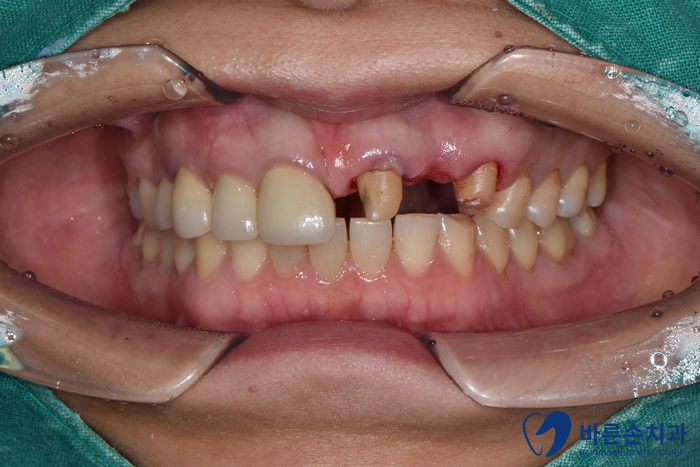

상태 체크를 위해 구내 사진과 엑스레이 촬영을 먼저 하였습니다!

치아 한 개가 상실되어 양 옆 치아를 연결해서 만든 보철물을 브릿지라고 하는데요.

브릿지가 빠져있고 남아있는 치아를 보니 연결해서 쓰던 치아 내부에 2차 충치가 생겼습니다.

사실 상태가 좋지 않아 발치 가능성이 높았지만 최대한 자연 치아를 살려보고자 치료를 들어갔어요 ‘-‘